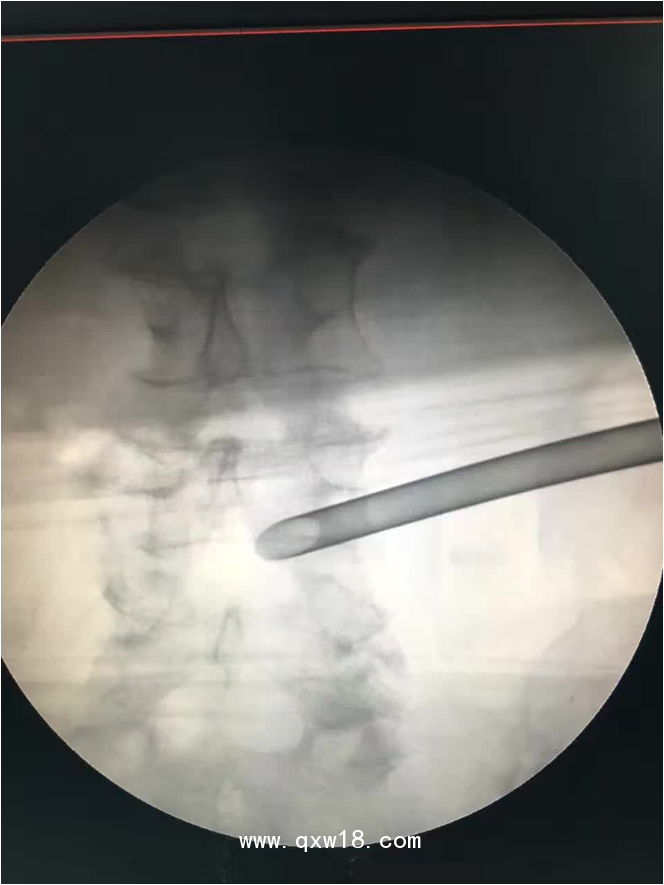

椎間孔鏡品牌椎間孔鏡椎間孔鏡技術(shù)椎間孔鏡培訓(xùn)產(chǎn)品說明:

portant; word-wrap: break-word !important;">椎間孔鏡手術(shù)圍手術(shù)期注意事項: